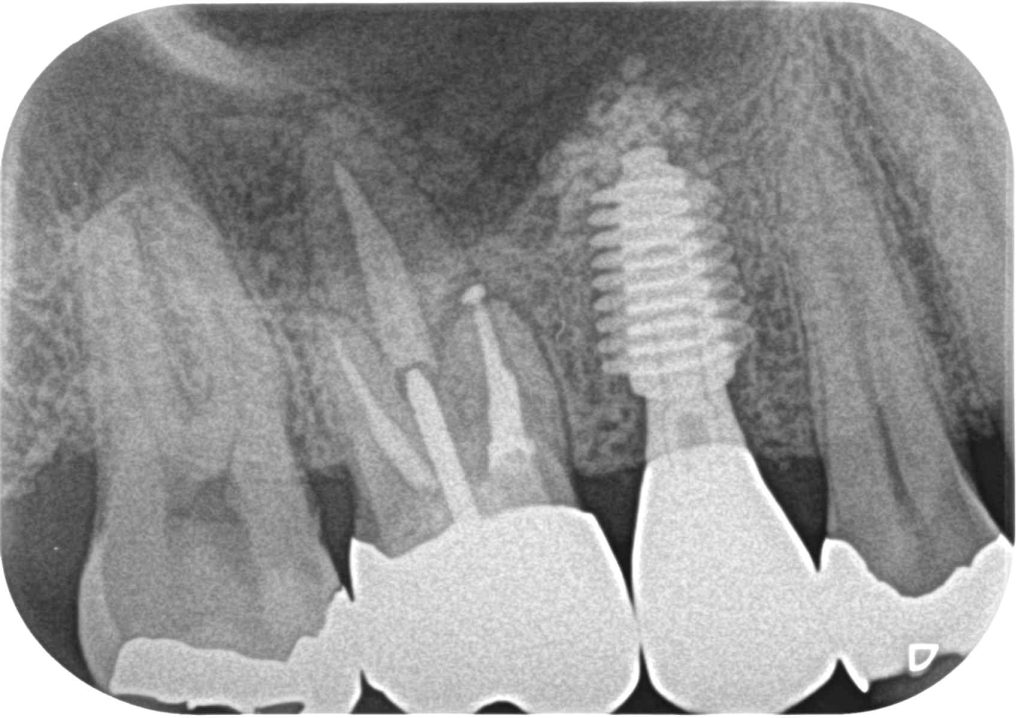

症例250代 男性 歯根破折にて右上5番を抜歯

治療前

治療後

ブリッジ・義歯・インプラントの選択肢を提案。

力学的に強く、両隣在歯に負担のかからないインプラントを選択。

ソケットリフト(上顎洞洞底膜挙上術)を行い、骨の高さを確保しインプラントを埋入。

オペ後、骨との密着値も良く、約3ヶ月後にはジルコニアを装着し終了。

リスクとしては外科的侵襲がある。デメリットは、保険外診療の為、経済的負担がある。

費用 64万(税込)(オペ・仮歯・最終補綴物まで含む)